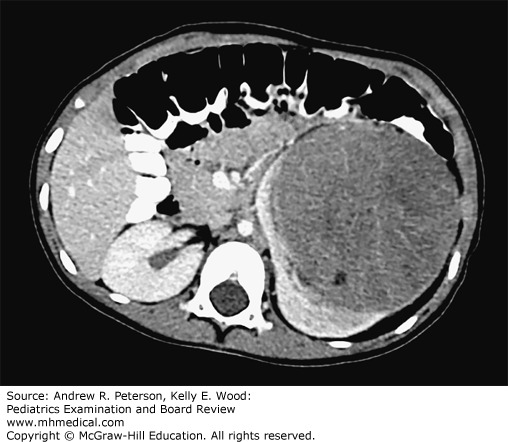

Wilms tumor. In this axial computed tomography image of the abdomen, there is a large encapsulated mass noted within the lower pole of the left kidney. The mass has no evidence of local infiltration or calcifications. Renal parenchyma, shown by contrast uptake, is pushed aside by the tumor, suggesting an intrinsic renal process. The left kidney remnant appears to be grasping or engulfing the lower-attenuation tumor, a finding sometimes described as a “claw sign.” (Used with permission from Adam D. Wolfe, MD, PhD.)